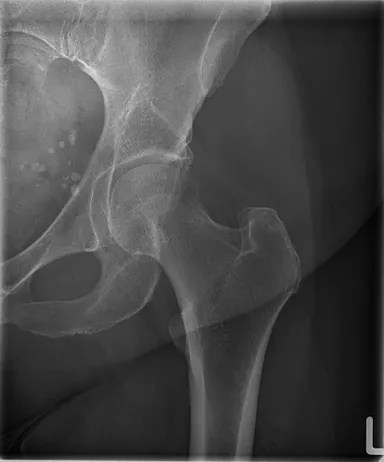

TRB 9020Hで撮影した大腿骨レントゲン写真

※84 kV HP mode 1.8 mAs, 0.12 sec Exposure Index: 367